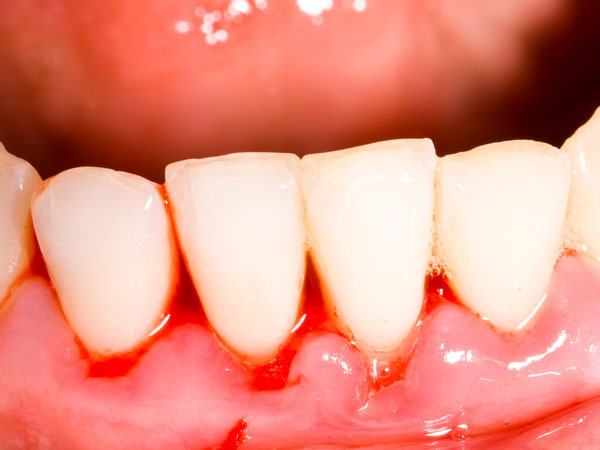

പല ദന്തഡോക്ടര്മാരും പല്ലെടുത്തു കളയാതെ പോടു വന്ന പല്ലില് നിര്ദേശിയ്ക്കുന്ന വഴിയാണിത്.

പല്ലില് പലര്ക്കും നടത്തേണ്ടി വരുന്ന ഒന്നാണ് റൂട്ട് കനാല്. കേടായ പല്ല് അടയ്ക്കാന് പറ്റാതെ വരുമ്പോള് ഇതിന്റെ അടിയില് നിന്നും കൃത്രിമ പള്പ്പിലൂടെ പല്ലിന് സപ്പോര്ട്ട് നല്കി ഇതു നില നിര്ത്തുന്ന രീതി.

പല ദന്തഡോക്ടര്മാരും പല്ലെടുത്തു കളയാതെ പോടു വന്ന പല്ലില് നിര്ദേശിയ്ക്കുന്ന വഴിയാണിത്. തികച്ചും സാധാരണ രീതിയിലുള്ള എന്ഡോഡോന്റിക് ചികിത്സ.

എന്നാല് ഈ ചികിത്സ പല്ലിന്റെ ആരോഗ്യത്തിന് നല്ലതെങ്കിലും ശരീരത്തിന്റെ ആരോഗ്യത്തിന് അത്ര നല്ലതല്ലെന്നാണ് പഠനങ്ങള് വെളിപ്പെടുത്തുന്നത്. പല തരത്തിലുള്ള ആരോഗ്യപ്രശ്നങ്ങള്ക്കും റൂട്ട് കനാല് ചികിത്സ വഴിയൊരുക്കും.

റൂട്ട് കനാല് ചെയ്യുന്ന പല്ല് അക്ഷരാര്ത്ഥത്തില് ചത്ത പല്ലാണ്. അതായത് വേരുകള് നഷ്ടപ്പെട്ട ഒന്ന് ഇതുകൊണ്ടുതന്നെ ഗുരുതരരോഗങ്ങള് വരുത്താന് ശേഷിയുള്ള ബാക്ടീരിയകളുടെ വളര്ച്ചാകേന്ദ്രമായി മാറാന് സാധ്യതയേറെയുള്ള സ്ഥലം. ചില പ്രത്യേക ഘട്ടങ്ങളിലാണ് ഇവ വളരുകയെന്നു മാത്രം.

ഇത്തരം ബാക്ടീരിയകള് രക്തത്തിലേയ്ക്കു കടക്കും. തുടക്കത്തില് ഇവ തിരിച്ചറിയാന് ബുദ്ധിമുട്ടാണ്. പിന്നീട് വര്ഷങ്ങള്ക്കു ശേഷമായിരിയ്ക്കും പല ഗുരുതരരോഗങ്ങള്ക്കും ഇവ കാരണമാകുന്നത്.

റൂട്ട് കനാല് ചെയ്യുമ്പോള് പല്ലിനുള്ഭാഗം പൊള്ളയാക്കി ഇതിനുള്ളില് ഒരു പള്പ് നിറയ്ക്കുന്നു. പല്ലിന്റെ വേരുകള് അറുക്കപ്പെടുന്നതു കാരണം ഇതിലേയ്ക്കുള്ള രക്തപ്രവാഹം ഉണ്ടാകില്ല.

എന്നാല് വേരുകളുടെ ചെറിയ ഭാഗങ്ങള് അപ്പോഴും അവിടെത്തന്നെയുണ്ടാകും. പല്ലിനടിയിലെ രക്തപ്രവാഹം നിലയ്ക്കന്നതു കാരണം ഭക്ഷണം ലഭിയ്ക്കാത്ത ബാക്ടീരിയകള് ഈ ഭാഗങ്ങളില് മറഞ്ഞിരുന്നു അതില് നിന്നുള്ള പോഷകങ്ങള് കൊണ്ടു വളരും.

ആന്റിബയോട്ടിക്സിനോ ശരീരത്തിന്റെ സ്വാഭാവിക പ്രതിരോധശേഷിയ്ക്കോ ഇവിടെ എത്തിപ്പെടാന് സാധിയ്ക്കാത്തതു കൊണ്ടുതന്നെ ഇവ ശക്തിയാര്ജിച്ചു വളരുക മാത്രമല്ല, ശരീരത്തിന് ദോഷകരമായ പല ടോക്സിനുകളും പുറപ്പെടുവിയ്ക്കുകയും ചെയ്യും.

യാതൊരു സ്റ്റെറിലൈസേഷനും ഇത്തരം ബാക്ടീരിയകളുടെ അടുത്തെത്താന് സാധിയ്ക്കില്ല. ഇവ പെരുകി പല്ലിന്റെ കീഴറ്റത്തും പെരിഡോന്റല് ലിഗ്മെന്റിലും അണുബാധയുണ്ടാക്കും. ഇത് കൂടുമ്പോള് താടിയെല്ലില് തന്നെ പോടുകളുണ്ടാക്കാം.

ഇത്തരം ബാക്ടീരിയകള്ക്ക് ശരീരത്തിന്റെ പ്രതിരോധശേഷി ശക്തമായിരിയ്ക്കുന്നിടത്തോളം ഒന്നും ചെയ്യാനാകില്ല. എന്നാല് ഇ്മ്യൂണിറ്റി കുറയുമ്പോള് ഇവ രക്തത്തിലേയ്ക്കു കടന്ന് മറ്റ് അവയവങ്ങളിലെത്തി രോഗങ്ങളുണ്ടാക്കും.

ഇത്തരം ബാക്ടീരിയകള്ക്ക് ഹൃദ്രോഗം, കിഡ്നി പ്രശ്നങ്ങള്, സന്ധിവേദന, ന്യൂറോസംബന്ധമായ അസുഖങ്ങള്, ലൂപ്പസ് പോലുള്ള ഓട്ടോഇമ്യുണ് രോഗങ്ങള് എന്നിവയ്ക്കു സാധ്യതയേറെയാണ്.